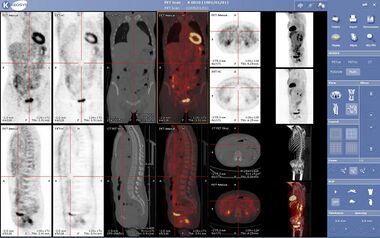

A nuclear medicine PET scan | |

الطب النووي Nuclear Medicine هو الفرع الطبي الذي تستخدم فيه النظائر المشعة radioisotopes لتشخيص بعض الأمراض وعلاج البعض الآخر، وقد سمي بالنووي نسبةً إلى نواة الذرة وهي مصدر الإشعاع المنبعث من هذه المواد المشعة ويعتبر الطب النووي من أحدث تطبيقات التكنولوجيا في المجال الطبي. Nuclear medicine imaging, in a sense, is "radiology done inside out" or "endoradiology" because it records radiation emitting from within the body rather than radiation that is generated by external sources like X-rays. In addition, nuclear medicine scans differ from radiology, as the emphasis is not on imaging anatomy, but on the function. For such reason, it is called a physiological imaging modality. Single photon emission computed tomography (SPECT) and positron emission tomography (PET) scans are the two most common imaging modalities in nuclear medicine.[1]